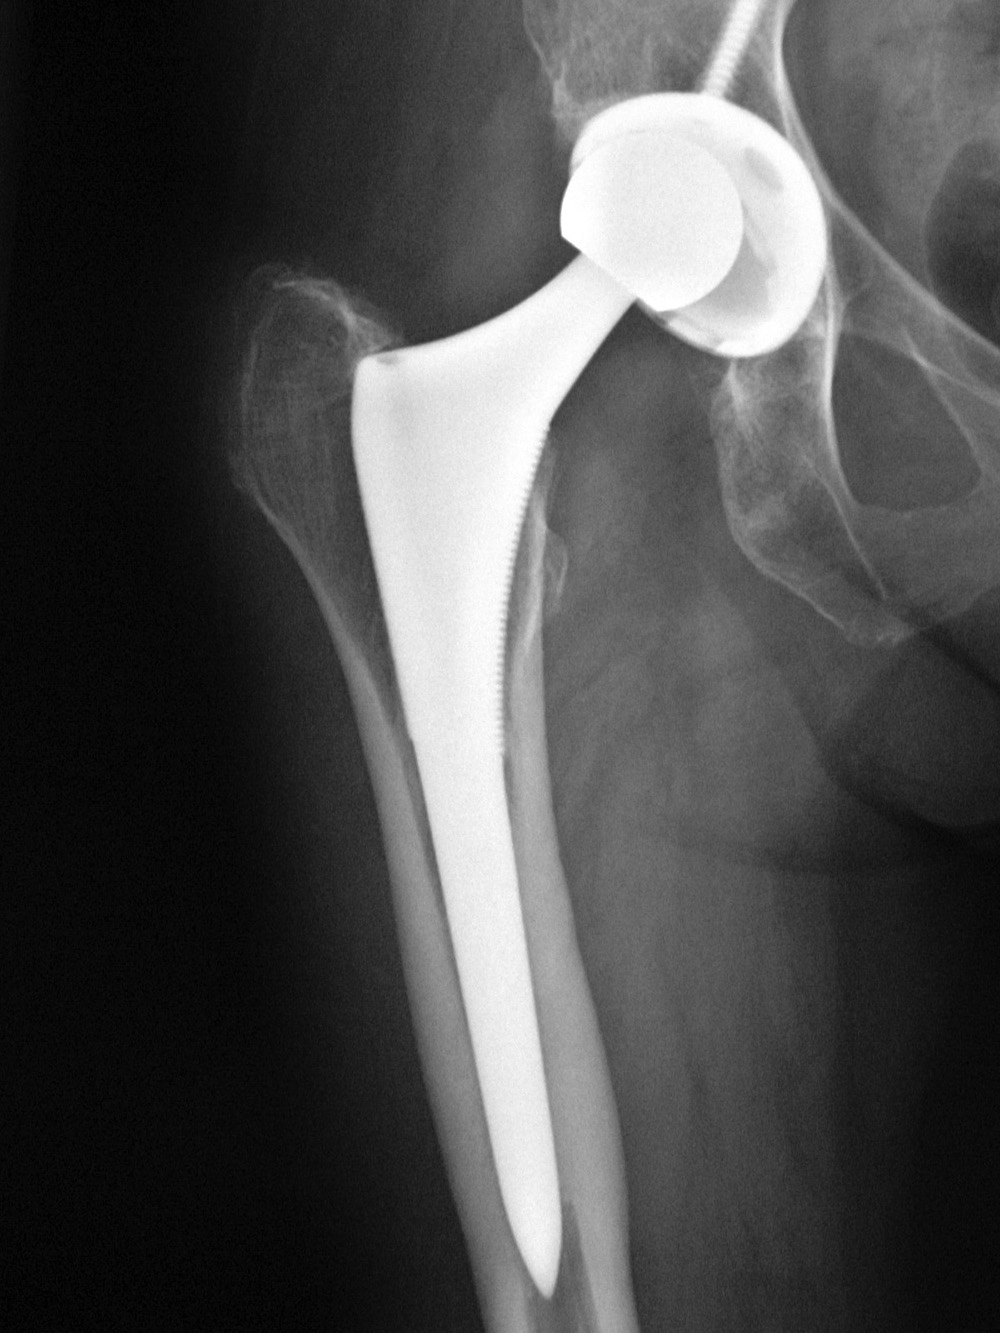

Non-infectious (aseptic) loosening of prosthetic components is

still the most common cause for hip implant failure and subsequent revision surgery. Loosening may be from mechanical stress with failure of the implant binding to the surrounding bone. There may be degradation of the cement-bone interface. Wear on the articular surfaces can produce tiny polyethylene particles or metallic particles which migrate from the joint and lessen bony healing giving subsequent osteolysis and eventual implant loosening (figure: focal osteolysis). The failure can occur at the prosthesis-bone interface, prosthesis-cement interface,

or cement-bone interface. Progressive development of radiolucent areas greater than 1 mm at these interfaces is worrisome for prosthesis loosening (figure: osteolysis at tip of femoral stem).

The femur has traditionally been divided into seven zones (1-7) on the anteroposterior (AP) view: zones 1-3 at the lateral side proximal to distal; zone 4 at the tip of the femoral stem; zones 5-7 at the medial side going distal to proximal. On the lateral view the femur is divided into zones 8-10 at the anterior side proximal to distal; zone 11 at the tip of the femoral stem; and zones12-14 on the posterior side going distal to proximal (figure: AP acetabular and femoral zones; figure: Lateral femoral zones). In any of these zones on any view, a radiolucent area greater than 2 mm is indicative of loosening (Berquist, 1995; Freiberg, 2001; Benjamin, 1994; Galante, 1998; Manaster, 1996; Deshmukh, 2019) (figure: femoral osteolysis).

Femoral osteolysis and loosening of noncemented total hip arthroplasty |

There is radiolucency (arrow) around the entire femoral stem with a sclerotic margin and eccentric positioning of the stem. There is also thinning of the lateral femoral cortex. From Benjamin, 1994 |